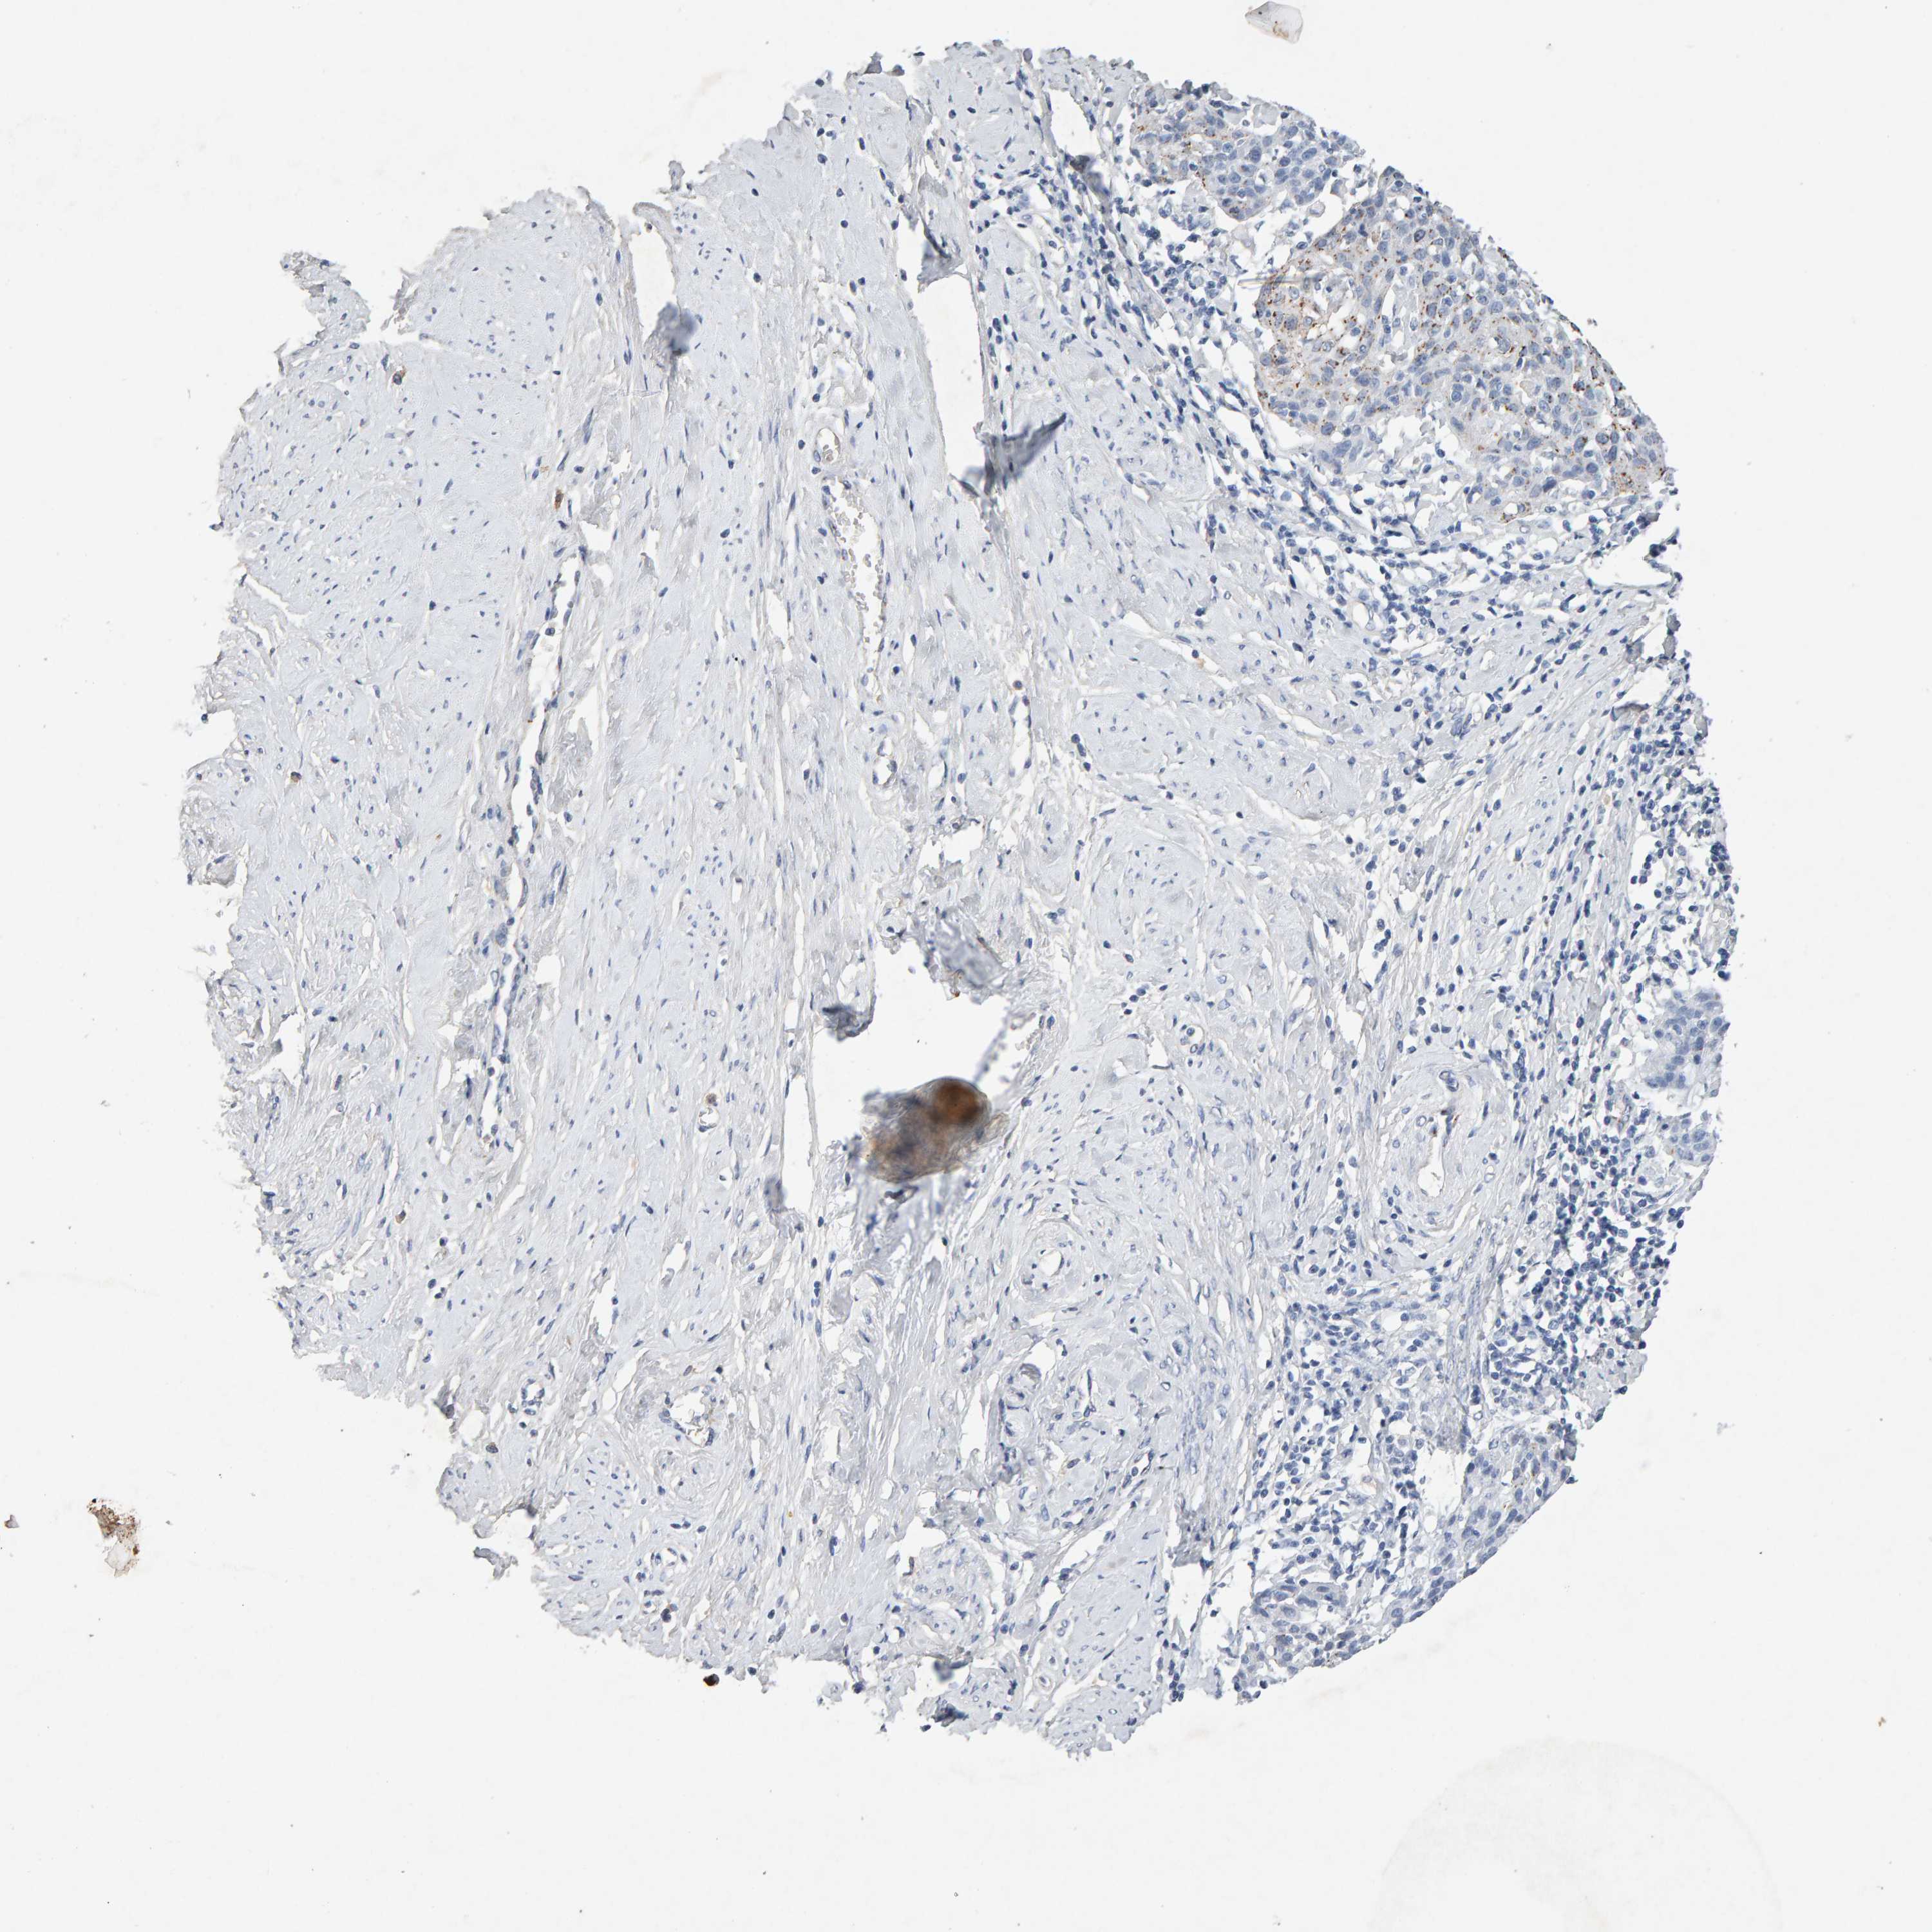

CERVICAL CANCER - Protein expressioni

A mouse-over function shows sample information and annotation data. Click on an image to view it in a full screen mode. Samples can be filtered based on level of antibody staining by selecting one or several of the following categories: high, medium, low and not detected. The assay and annotation is described here.

Note that samples used for immunohistochemistry by the Human Protein Atlas do not correspond to samples in the TCGA dataset.

Antibody stainingi

Antibody staining in the annotated cell types in the current human tissue is reported as not detected, low, medium, or high, based on conventional immunohistochemistry profiling in selected tissues. This score is based on the combination of the staining intensity and fraction of stained cells.

Each image is clickable and will lead to virtual microscopy that enables deeper exploration of all samples and also displays staining intensity scores, fraction scores and subcellular localization as well as patient and tissue information for each sample.

Antibody CAB022442

Antibody CAB022443

Squamous cell carcinoma, NOS

Adenocarcinoma, NOS